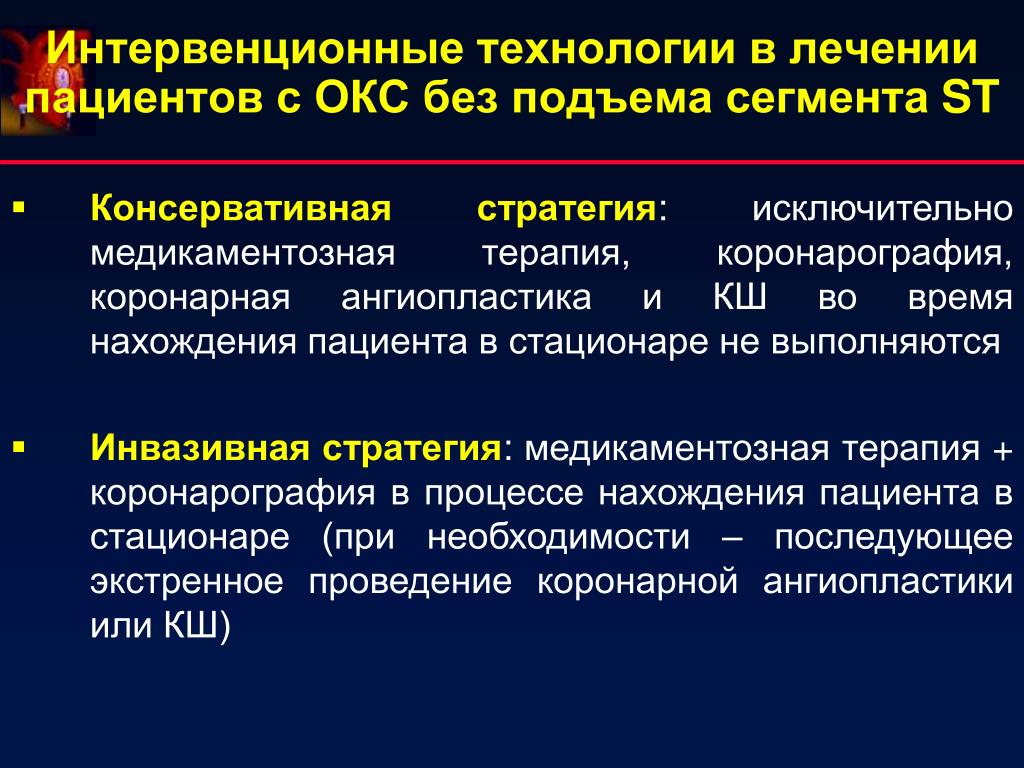

Интервенционная коронарография представляет собой высокотехнологичную процедуру, которая используется для диагностики заболеваний сердца и сосудов. Этот метод позволяет врачам точно оценить состояние коронарных артерий и выявить возможные патологии, такие как атеросклероз или стеноз. Современные подходы к интервенционной коронарографии значительно повысили эффективность лечения, снижая риск осложнений и обеспечивая более точную диагностику.

Стентирование коронарных артерий

Стентирование коронарных артерий: как тонкая трубочка меняет судьбы пациентов?